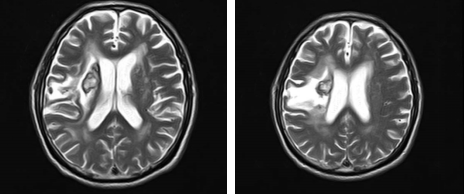

4月1日,入院磁共振检查为右侧基底节区及右顶叶出血吸收齐改变;两侧基底节区腔隙性脑梗塞;右侧基底节区液化灶;现存功能障碍为左侧肢体活动受限,日常生活功能减退,无法站立、平衡不稳。